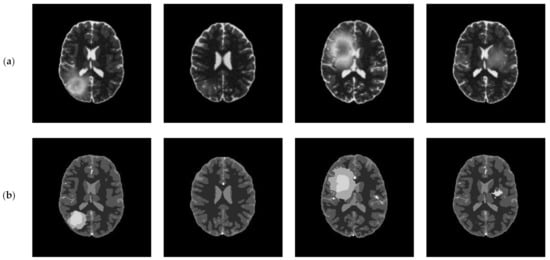

4.6. Experimental Results on BRATS Database

In this subsection, we applied the proposed algorithm to the BRATS (Multimodal Brain Tumor Image Segmentation Benchmark) database. The BRATS database (http://www.imm.dtu.dk/projects/BRATS2012/data.html, accessed on 25 September 2021) is compiled from the international brain tumor segmentation challenge in MICCAI 2012 conference. It is a widely used database and composed of multi-contrast brain MR scans of 25 low-grade and 25 high-grade glioma cases and the corresponding ground truth. Each case includes four modalities—T1, T1c, T2, and FLAIR [44]—and each MR scanning sequence contains more than one hundred images. Figure 20 presents an example of brain MR images from BRATS. Figure 20a shows the original images and the corresponding ground truth is displayed in Figure 20b.

Figure 20.

An example of original images and ground truth from BRATS: (a) original images, (b) ground truth.

The performance of the proposed algorithm on BRATS was compared with other segmentation algorithms in terms of the uniformity measure, misclassification error, Hausdorff distance, and Jaccard index. Figure 21 shows the average evaluation values for different algorithms. It can be observed that the proposed algorithm achieves excellent results in terms of the uniformity measure and Hausdorff distance, as shown in Figure 21a,c, which are obviously better than those of other algorithms. From Figure 21b,d, the proposed algorithm also performs best, followed by LL-DCE.